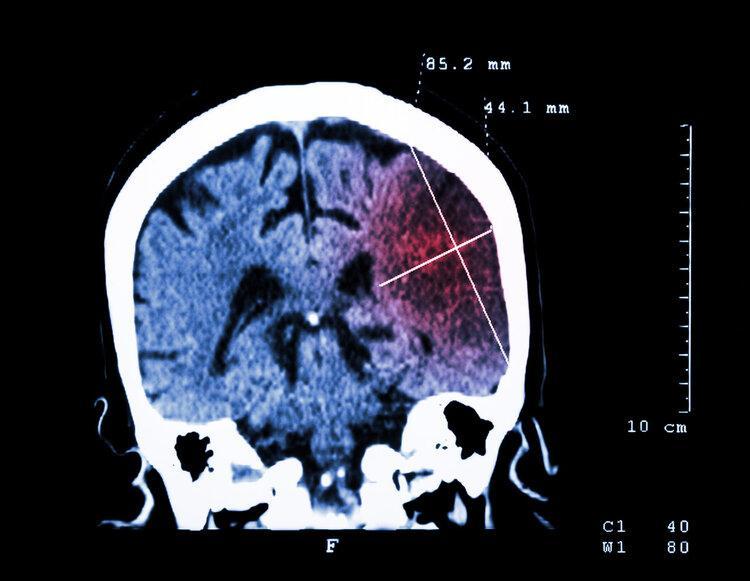

一天正喫飯時,劉先生突然出現眼前黑蒙、頭部劇痛等症狀,沒一會兒人就暈過去了,妻子只好趕忙把他送到了醫院,結果被診斷爲腦梗。

急性腦梗是最常見的腦卒中類型,是由於斑塊侵蝕、腦部血供不足導致的腦組織缺血、細胞損傷甚至死亡。